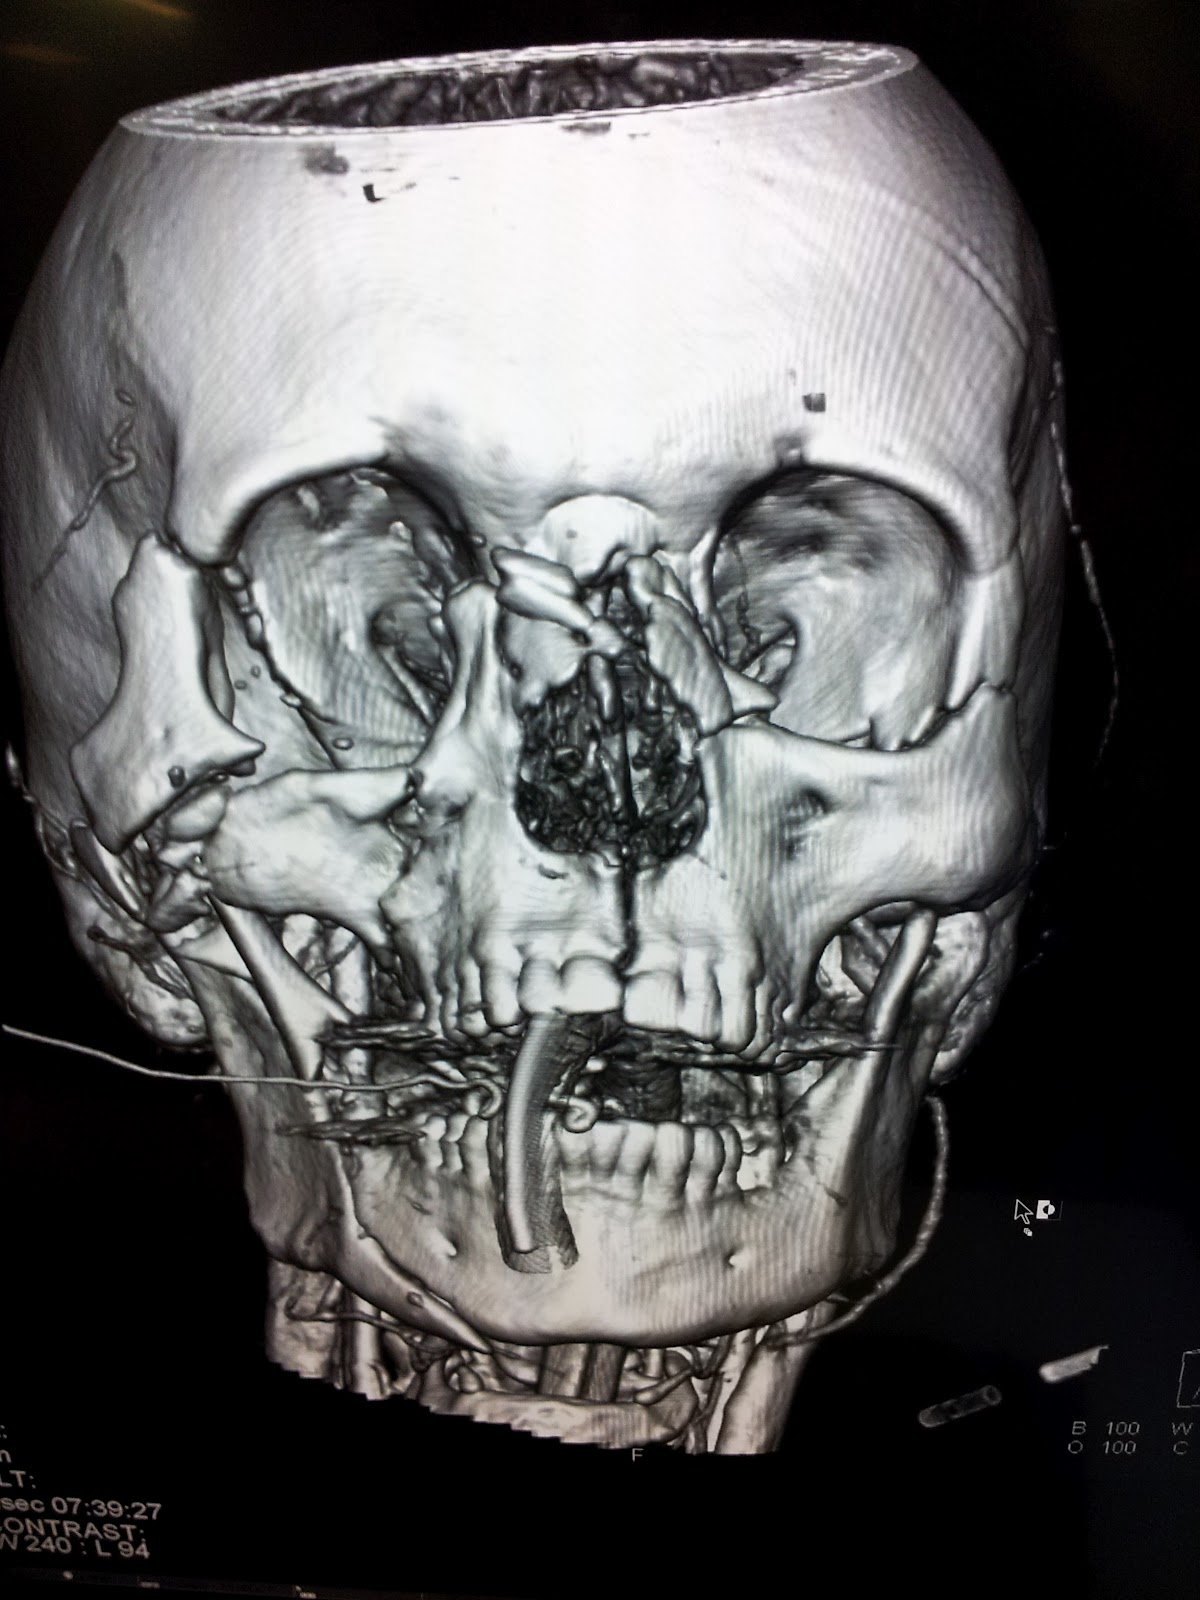

Of course, on my first clinical day, I walk in at 0745 and everyone’s in one of the five trauma rooms. A male bicycle rider vs a truck. Truck wins, every time…..I don’t want to upset anyone with the graphic details, but I spent the morning lead-gowned as an observer in the Interventional Radiology suite watching them coiling hemorrhaging mid-face arteries.. Though I was a complete stranger, the Aussie crew couldn’t have been more professional or accommodating; even allowing me to shoot pictures of them busy at their life-saving work….And what an amazing privilege, to be allowed a glimpse inside their fascinating environment…. Here are a few shots, while still trying to keep it family friendly…

| CT 3D, Lots of facial trauma if you know where to look… |

For the Medical people following along, I have to say, it’s been a wonderful and humbling experience to be back in the Tertiary world after 20 or so years.. I’m one of the “senior” team members now, but everyone is extremely helpful; and luckily, they aren’t expecting me to run the team. Unless I want to, of course…! Teaching Residents again has been very rewarding; I have seen a lot over 20 years it seems……The clinical conditions are similar, but the management has changed somewhat. We are using lots of pressors, Adrenaline and Noradrenaline (no “Epi” down under!), Propofol infusions, lots of Ketamine, even in adults; auto-infusion devices..But no Dilaudid, IV Benadryl, Lorazepam or Quinalones…Ultrasound guided everything..central lines, arterial lines…Very high acuity, very invasive and intellectually challenging for sure! And the 64 slice scanners with near instantaneous 3-D reconstruction provide very rapid confirmation, or humiliation of your clinical diagnoses…